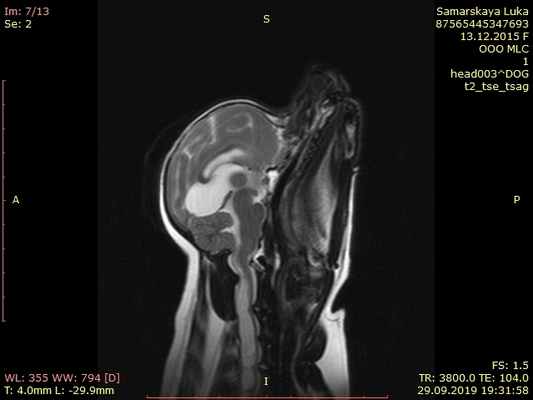

МРТ краниовертебрального сочленения в сагиттальной плоскости (А) и художественное исполнение (Б).

Показаны покровная мембрана (стрелка) и поперечная связка атланта (толстая стрелка).

БА — базион; ОП — опистион; ПМем — передняя атланто-затылочная мембрана; ЗМем — задняя атланто-затылочная мембрана;

З—Зуб; Ост2 — остистый отросток С2;ПД — передняя дуга атланта (тонкая стрелка); ЗД — задняя дуга атланта. Крестообразная, поперечная, крыловидные и добавочные связки.